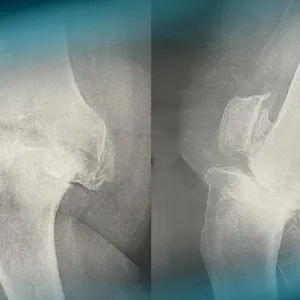

A 68-year-old woman has been suffering from mechanical bilateral knee pain for the past 6 years. The x-rays reveal complex right knee arthritis with ligament deficiency. How would you classify it and how would you manage this condition?